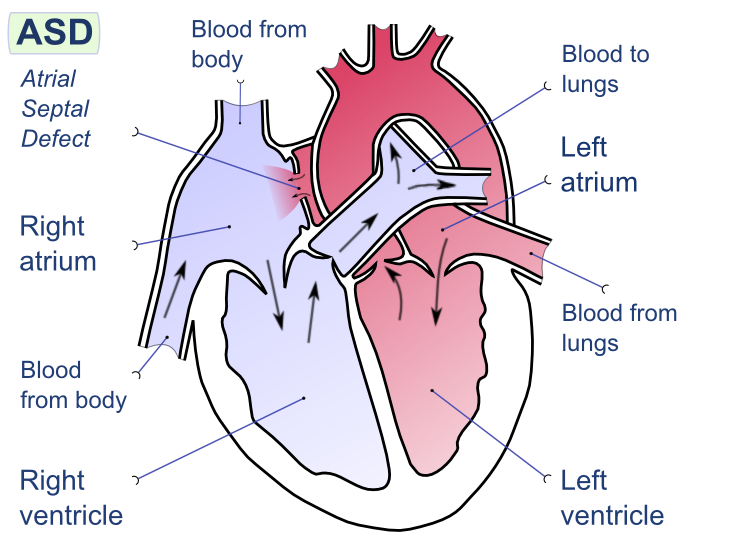

Hypoxemia – is a condition involving abnormally low blood oxygen levels. It can lead to bluish skin, difficulty breathing and fast heart rate. Apart from sleep apnea and higher altitudes, hypoxemia can be also be caused by many underlying illnesses, mainly lung and heart related especially in conditions of low environmental oxygen, diffusion impairment, hypoventilation, right -to left atrial shunting (image below).

Respiratory failure is a critical condition that develops due to low blood-oxygen levels in the bloodstream that makes involuntary tasks like breathing almost impossible to do on your own. The low blood-oxygen levels results due to inadequate gas exchange during pulmonary circulation, which could be because of pump failure or lung failure. Pump failure is a ventilation failure which causes hypercapnia whereas lung failure is gas exchange failure causing hypoxemia. It can also de defined as arterial oxygen tension (Pao2 < 60mmHg) or arterial carbon dioxide tension (PaCO2).

Type I: – involves a ventilation/perfusion mismatch that causes untreatable hypoxemia (PaO2). Another characteristic of type I respiratory failure is alveolar flooding.